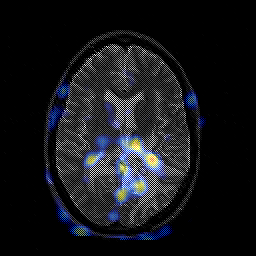

Glioblastoma multiforme overlay -- Slice #30

[Home][Help][Clinical][Tour 1][Tour 2][Tour 3] Slice 30